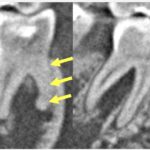

レントゲンでわかること、わからないこと

歯髄炎はレントゲンでわかるのでしょうか?結論からいうと、歯髄炎が起こっているかどうかは、レントゲン写真ではわかりません。しかし、過去に受けた治療の範囲、虫歯の深さ、歯髄腔の状態など、レントゲン写真からは多くの情報を得ることができます。また、歯の根が複数本ある大臼歯の場合、一部の根は死んでしまい根の先に膿があり、別の根の神経は生きている、という場合もあります(部分壊死)。そのような場合、CTによる三次元的な画像検査が診断のために非常に有用といえます。